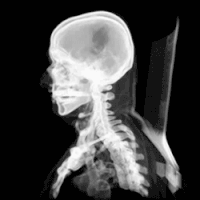

تشوه خياري والذي يعرف أيضا بـ:تشوه آرنولد خياري (بالإنجليزية: Arnold–Chiari malformation) أو (ACM) هو حالة مرضية تحدث عند وجود تشوه خلقي نادر يصيب المخيخ وحجرة المخيخ الخلفية أو إذا كان حجم الجمجمة بالغ الصغر مما يؤدي إلى تغيير في موقع اللوزة المخيخية ودفعها نحو الأسفل من خلال الثقبة العظمى وقد يؤدي أحيانا إلى استسقاء رأس غير متواصل[1] نتيجة لانسداد في جريان السائل الدماغي الشوكي.[2][3]